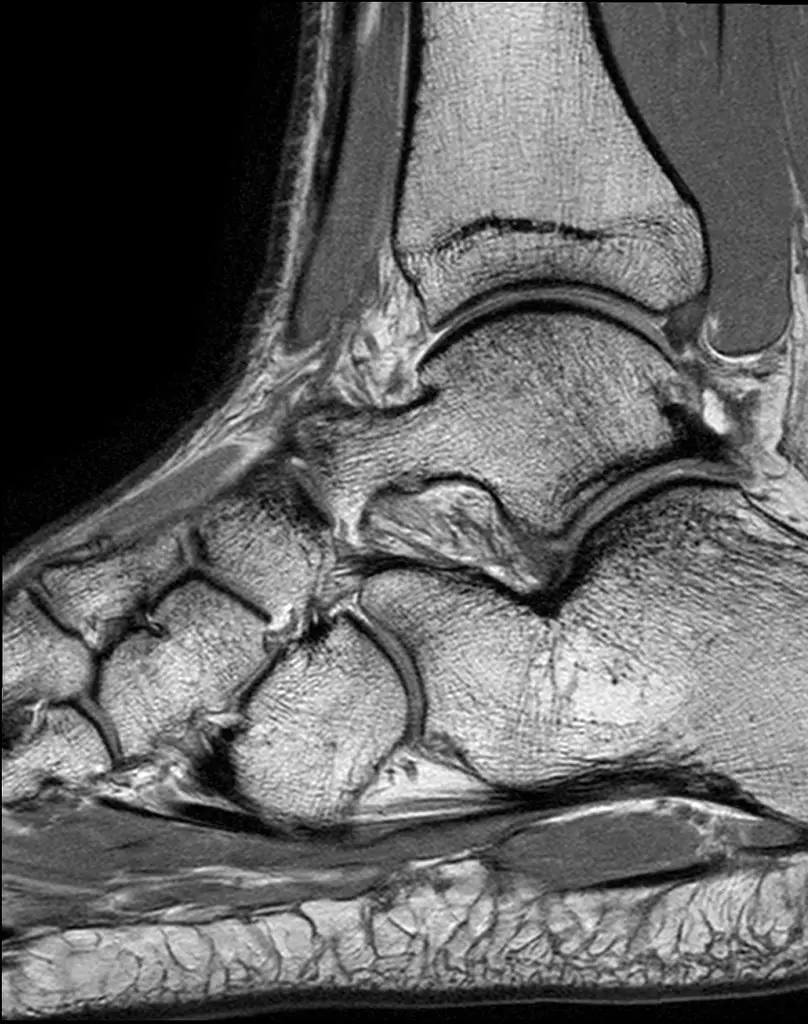

МРТ голеностопного сустава

Визуализация костей голеностопного сустава, сухожилий, связок, регионарных мышц.